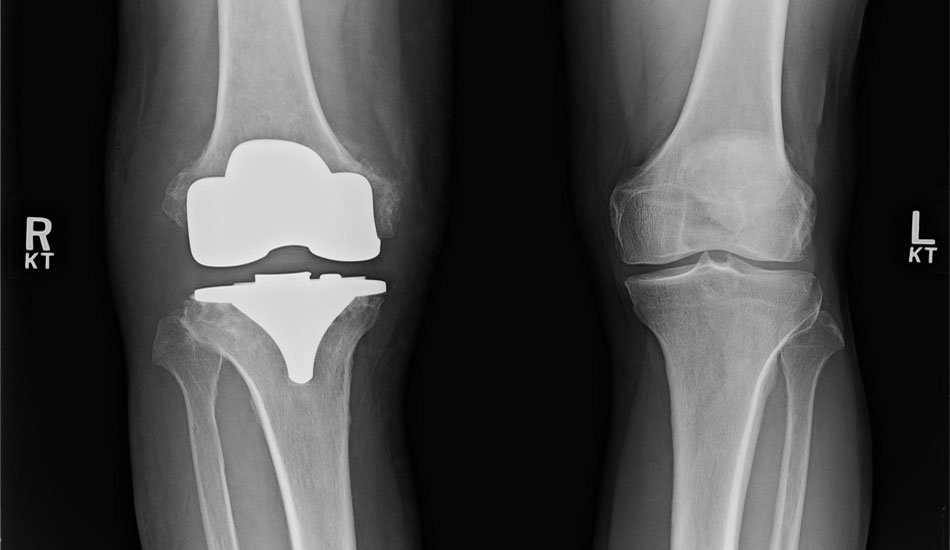

Η ολική αρθροπλαστική (αντικατάσταση) του γόνατος περιλαμβάνει την αφαίρεση λεπτού στρώματος της αρθριτικής (φθαρμένης) αρθρικής επιφάνειας του μηριαίου και της κνήμης και την αντικατάστασή του με μέταλλο το οποίο καθηλώνεται στη θέση του με ειδικό οστικό τσιμέντο. Μεταξύ των δύο μεταλλικών επιφανειών τοποθετείται ένα πλαστικό ένθετο (πολυαιθυλένιο).

Ασθενείς που θα ωφεληθούν από μια ολική αρθροπλαστική γόνατος είναι αυτοί που έχουνε σοβαρή και εκτεταμένη αρθρίτιδα στο γόνατο που τους προκαλεί πόνο στο περπάτημα, στις σκάλες ακόμα και όταν κοιμούνται τη νύχτα και περιορίζει τις καθημερινές δραστηριότητες.

Η ολική αρθροπλαστική γόνατος έχει εξαιρετικά αποτελέσματα του και είναι η πιο συχνή αντικατάσταση μιας άρθρωσης στο σώμα. 90% των ασθενών που υποβάλλονται σε ολική αρθροπλαστική γόνατος αναφέρουν άριστα αποτελέσματα με σημαντική βελτίωση στη λειτουργία και απώλεια πόνου. 95% των ολικών αρθροπλαστικών γόνατος λειτουργούν καλά μετά από 10 χρόνια και 80-85% εξακολουθούν να λειτουργούν καλά μετά από 20 χρόνια.